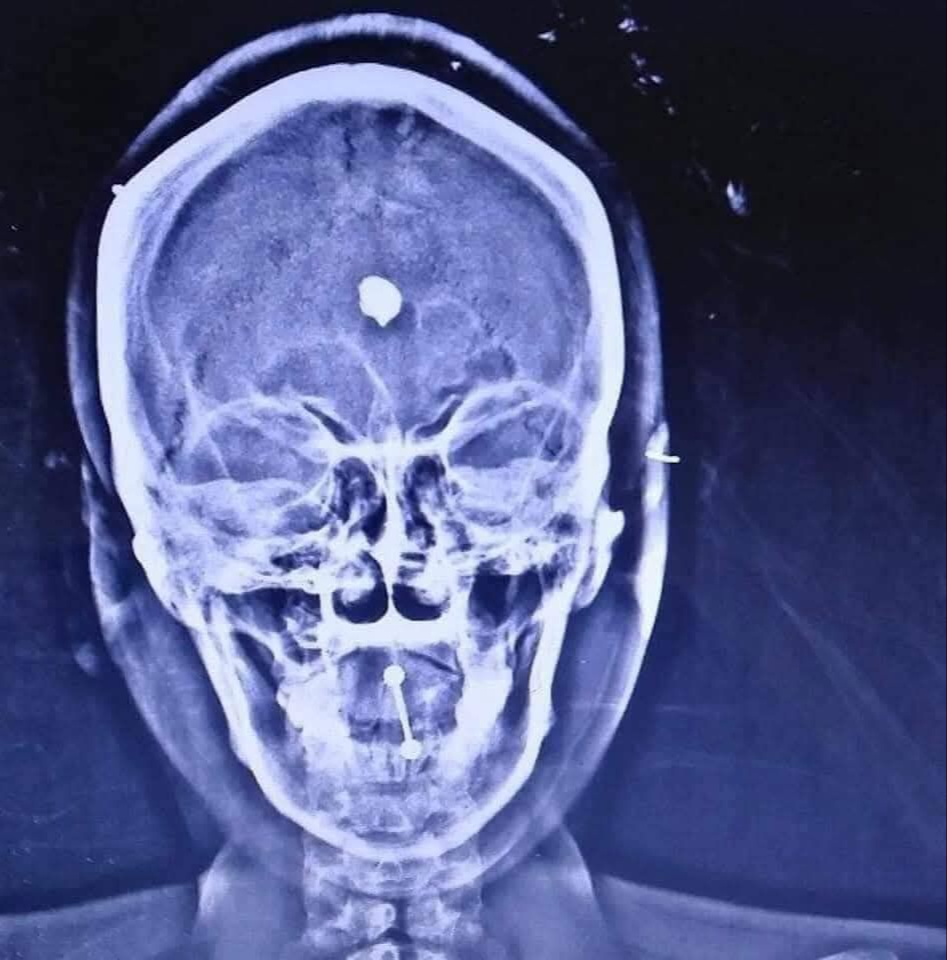

El delito ocurrió el 19 de febrero de 2018, en el interior de un domicilio ubicado en el fraccionamiento Arcila, en Ciudad del Carmen. Presuntamente, Gabriela “N” agredió a la víctima con un martillo y posteriormente le disparó en varias ocasiones con un arma de fuego, causándole diversas lesiones.

Minutos después, se relacionó a José “N”, señalado como quien aparentemente trasladó a la víctima en la cajuela de un automóvil Nissan Versa hacia un rancho cercano a la carretera Escárcega–Villahermosa, donde la abandonó.

La víctima fue agredida con un martillo y un arma de fuego.

La víctima fue agredida con un martillo y un arma de fuego. / Especial